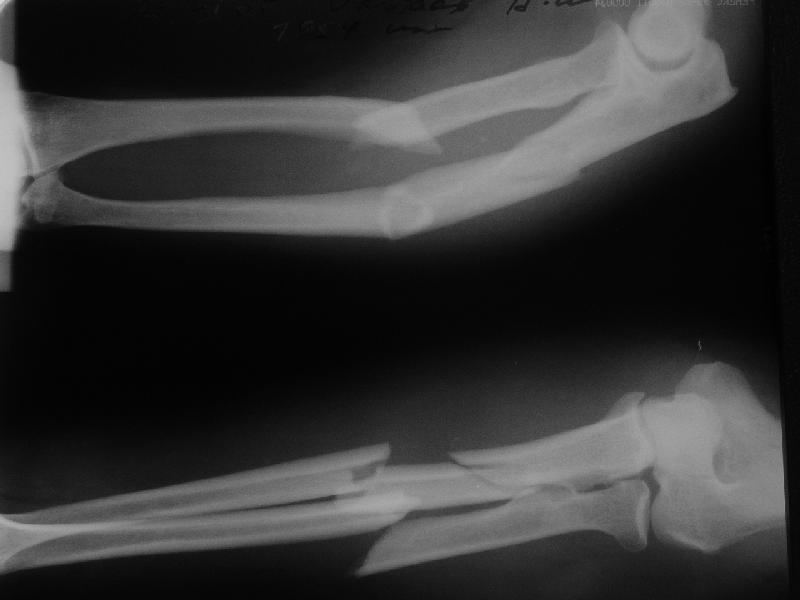

Мужчина 51 г., поступил через 4 дня после производственной травмы (груз упал на руку) уже в гипсе.

Был очень большой отек, 2 участка некроза по 2-3 см, с сукровичным отделяемым. Боялись развития синдрома сдавления. Чувствительных расстройств не было. Оставили в гипсе временно, прошла неделя, вроде обошлось. Гноя нет, отек спадает. Какой выбрать метод оперативного лечения? В основном выбор, наверно, между закрытым интрамедуллярным и чрескостным остеосинтезом?

A male 51 years old admitted to our unit 4 days after industrial trauma (a heavy piece of metal fell on the forearm) already in a plaster cast. Swelling was so significant that compartment syndrome was expected but he still has been demonstrating good sensation and movement of fingers. Also there were 2 sites of skin necrosis 3x1 cm, with serous drainage. He was left in the plaster for a week - looks better now. Swelling decreased, no pus. What surgical option should be preferred? As i realize, primary alternatives are closed nailing and external fixation? THX in advance.